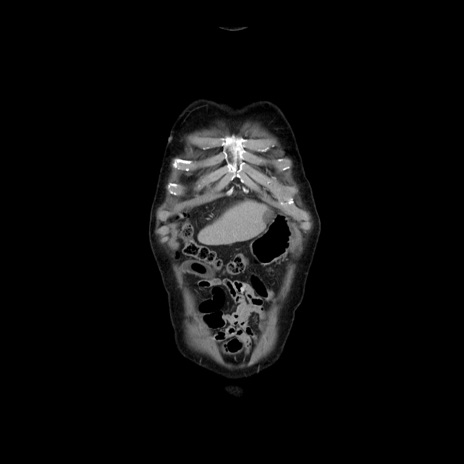

横断像